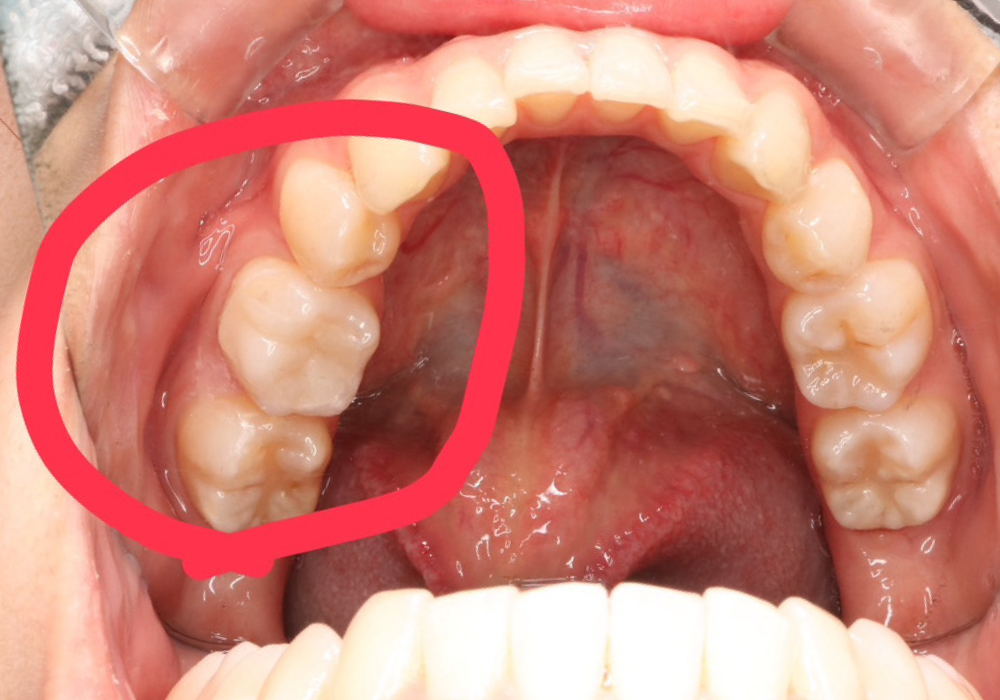

■治療抜歯即時

抜歯して当日に抜歯部位にインプラント手術を行うこと

抜歯

インプラント手術